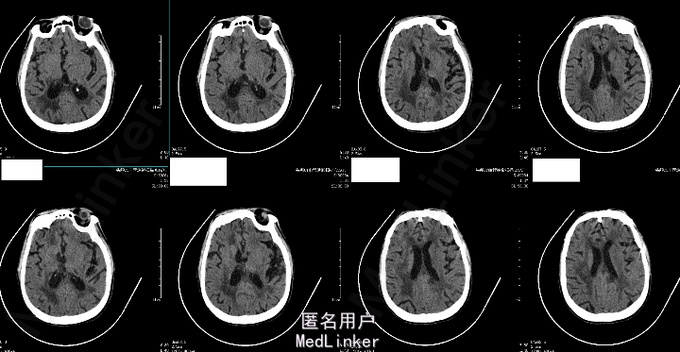

查体:T 37.0℃,P 82bpm,R 20bpm,BP 180/109mmHg。 专科情况:意识模糊,自主睁眼,无法言语,呼之不应,不配合检查。颈软;无强迫头位。眼裂对称,眼睑无下垂,眼球位置居中,各向活动五受限,未见眼球震颤,双侧瞳孔等大等圆,对光反射灵敏。双侧额纹对称,右侧鼻唇沟变浅。混合性失语,饮水呛咳。四肢肌肉萎缩,四肢肌张力增高,疼痛刺激后右上肢肌力1级,右下肢肌力2级,左侧肢体肌力2级。双侧Babinski征、Chaddock征阳性。 辅助检查:2015-06-03外院头颅MR:1.左侧额顶叶急性脑梗死;2.右侧颞枕叶、小脑、双侧基底节区及脑桥软化灶;3.脑白质缺血,脑萎缩。 2015-06-25我院头颅CTA:1.右侧小脑半球、右侧枕叶、双侧基底节区、放射冠及半卵圆中心多发缺血、梗死、软化灶;脑白质变性;脑萎缩。2.基底动脉延长、扩张,双侧椎动脉颅内段扩张(基底动脉管径最大约6mm,末端超出鞍背范围;右侧椎动脉颅内段管径最大约5mm,左侧椎动脉颅内段管径最大约4.5mm),考虑椎-基底动脉延长扩张症。3.脑动脉硬化;左侧大脑前动脉A2段闭塞;右侧颈内动脉海绵窦段、右侧大脑前动脉A2段、左侧大脑后动脉局限性狭窄;右侧颈内动脉海绵窦段钙化斑块;右侧大脑后动脉汇入右侧颈内动脉,考虑先天变异。